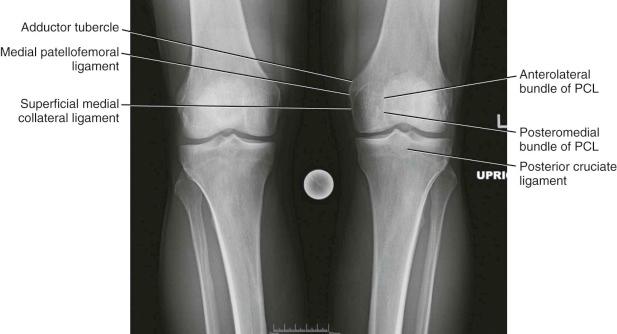

Radiologic Landmarks

( Figs. 7-12 through 7-15 )

FIGURE 7-12, Radiologic landmarks of the knee. PCL, Posterior cruciate ligament.

FIGURE 7-13, Radiologic landmarks of the knee.

FIGURE 7-14, Radiologic landmarks of the knee. ACL, Anterior cruciate ligament; MCL, medial collateral ligament.

FIGURE 7-15, Radiologic landmarks of the knee.